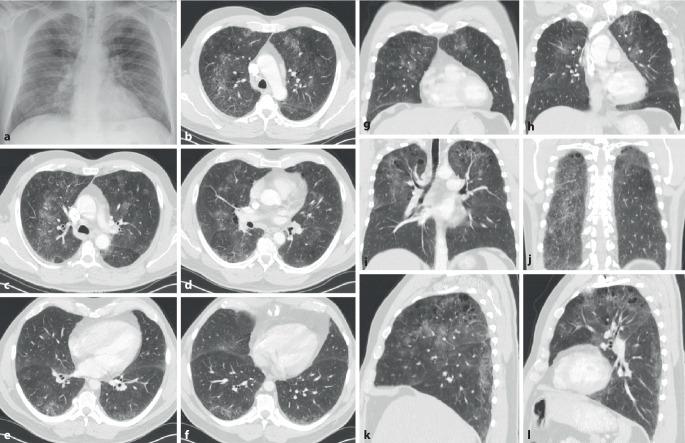

Rheumatic diseases frequently present with pulmonary involvement. All anatomic structures of the lungs can be affected. Interstitial lung diseases are characterized by a system of patterns evident in high-resolution computed tomography (HR-CT) scanning of the lungs. The HR-CT pattern can differ between rheumatic diseases.

风湿性疾病常伴有肺部受累。肺的所有解剖结构均可受到影响。间质性肺疾病的特征是在肺部高分辨率计算机断层扫描(HR-CT)中可见一系列明显的影像表现。不同风湿性疾病的HR-CT影像表现可能有所不同。

肺部受累很常见且与预后相关。肺部受累的概述显示,炎性风湿性疾病的受累解剖结构以及间质性疾病的影像表现具有高度变异性。提供了主要诊断结果的概要。

结论

此处提及的每种风湿性疾病都可能与肺部受累相关。因此,在首次诊断以及随访期间,必须进行系统的诊断评估。除了临床症状和肺功能外,肺部HR-CT对诊断起决定性作用。